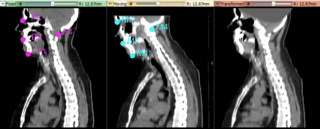

- Qualitative evaluation of deformable registration, such as shared cursor or split screen